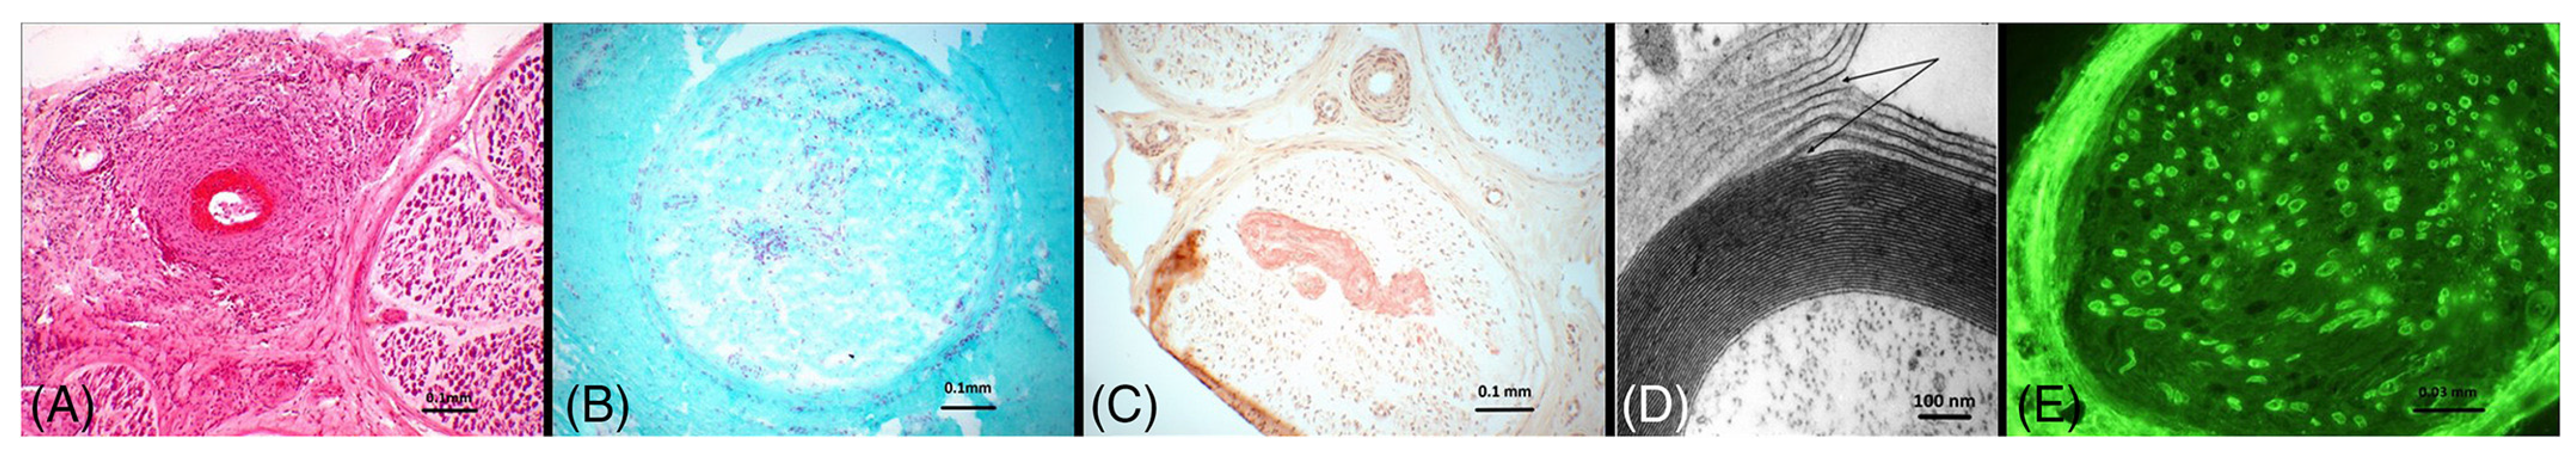

2.1.1. Vasculitis

2.2.1. Amyloidosis

2.3.1. Chronic Inflammatory Demyelinating Polyneuropathy (CIDP)

2.3.2. Paraproteinemic Neuropathy